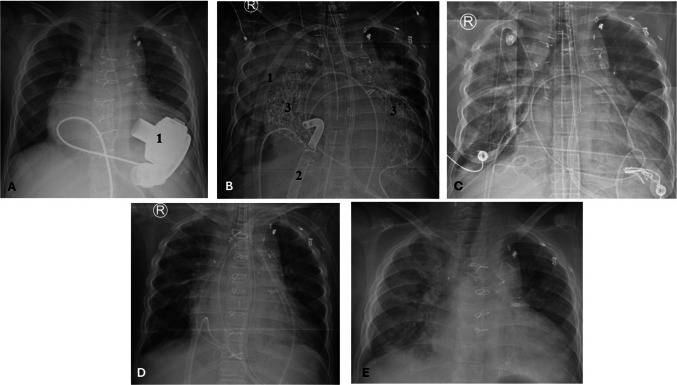

We describe a case of profound coagulopathy during orthotopic heart transplantation in a cyanotic single ventricle pediatric patient with an intracorporeal continuous flow ventricular assist device performed on bivalirudin for heparin-induced thrombocytopenia. This was successfully managed with central veno-arterial extracorporeal membrane oxygenation and hemofiltration as an adjunct to treat bivalirudin-induced coagulopathy due to lack of a reversal agent for bivalirudin.